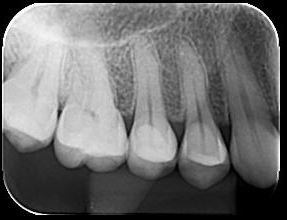

O Exame Radiográfico evidencia Perda Óssea

Exame Radiográfico

O exame Radiográfico é muito importante, deve ser observado o volume e a posição da crista óssea para que se tenha uma melhor condição de previsibilidades, viabilidade e escolha da técnica a ser utilizada. (RX Periapical e Interproximal)